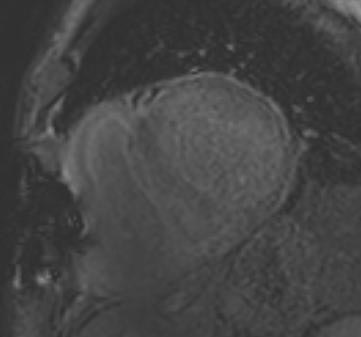

We have tried hard to optimize the MR images of our patients, but the difficulties of respiratory compliance and arrhythmia have limited our success. Detecting scar tissue is one of the most common tasks, and CMR not only reveals the existing damage but also can help to plan further interventions. Signs of inflammation or storage diseases are also often requested, next to a precise volumetry of valvular insufficiencies.

In my practice I have certainly gained more knowledge in working with CMR, and I continue to get more ideas about how to use it to answer specific questions, such as late enhancement for detecting scar tissue, T2-weighted imaging for edema, short axis view, and aortic and pulmonary flow for precise volumetry.